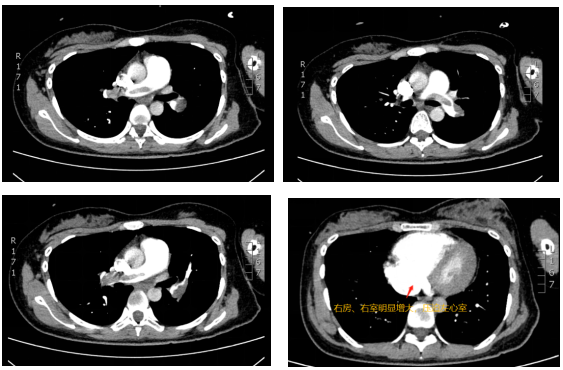

肺部CTA:两肺动脉主干及分支多发肺栓塞、右房、右室明显增大图1

图1  患者肺部CTA